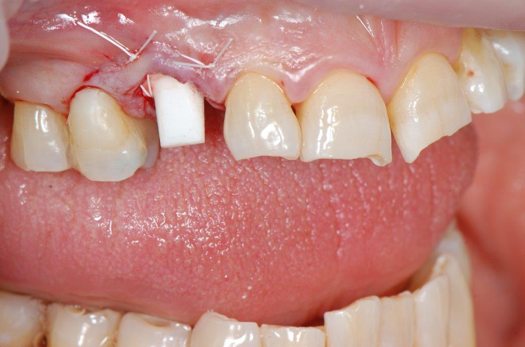

Fig 20. Immediately after extraction and placement.

Figure 20

Fig 21. Retainer provisional.

Figure 21

Occasionally dentists are presented with extreme challenges with long-term restorations and replacing missing teeth. Dentists must evaluate the patient's condition, develop optimum long-term oral health, and attempt to meet the patient's expectations. Figure 18 showed a class III malocclusion with deep bite, multiple abfractions, and less-than-ideal occlusal plane, but the patient wanted to replace his maxillary right canine only. A discussion with the patient regarding occlusal disharmonies and comprehensive recommendations for full-mouth rehabilitation revealed that the patient had a limited budget for dental care. The patient understood the ramifications of his comprehensive dental needs not being affordable. Decisions were made to atraumatically remove the maxillary right canine (Figure 19) and immediately place a ceramic dental implant (Figure 20). Polytetrafluoroethylene (PTFE) 4-0 sutures were placed to help support soft tissues, and then a full-arch Essix-style retainer with a flowable composite facial veneer was used to provide some esthetics during the patient's healing phase (Figure 21). The implant and the retainer were not to be in contactthe retainer may occlude with the opposing dentition and also be passive in relation to the ceramic implant.